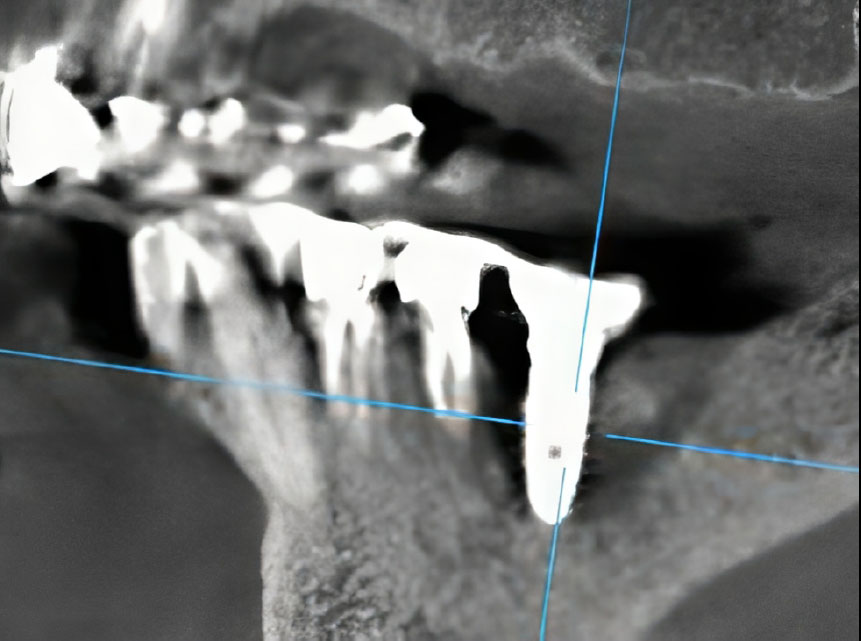

Intraoral examination revealed localized gingival erythema and edema in the area of teeth #45 and #46. Palpation was painful and elicited a purulent discharge from the peri-implant sulcus of #46. Periodontal probing detected deep pockets (>8mm) with palpable, rough, and exposed bone. Notably, the dental implant at site #46 was initially clinically stable. Cone-Beam Computed Tomography (CBCT) imaging revealed a sclerotic bone pattern with increased bone density surrounding the implant, along with a distinct focus of bone destruction adjacent to the implant apex at site #46, consistent with osteonecrosis (Figs. 1, 2). Based on the AAOMS diagnostic criteria, a diagnosis of Stage 2 Medication-Related Osteonecrosis of the Jaw (MRONJ) was established.

Sagittal CT projection revealing a well-defined focus of bone destruction in the region of tooth #46 with peri-implant involvement.